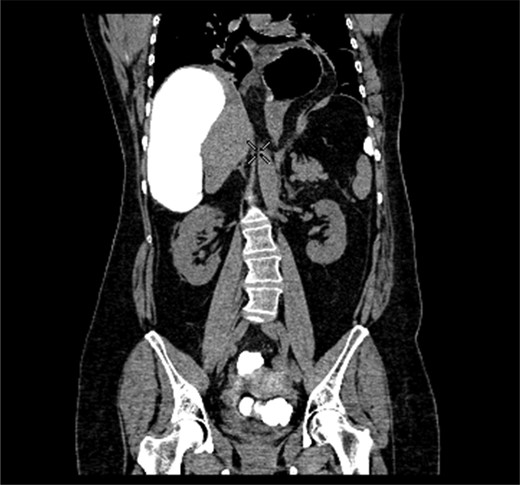

A 58-year-old female with a past medical history of a large intrathoracic hiatus hernia presented to her general practitioner and was subsequently referred to our surgical department with symptoms of sudden onset severe epigastric pain associated with vomiting and abdominal distension. Her abdomen was generally tender, maximally in the epigastric region, although she was not peritonitic. The admission erect chest radiograph showed a large hiatus hernia and an elevated right hemidiaphragm with a large loop of distended bowel (Fig. 1). Subsequent computed tomography (CT) scan demonstrated an almost completely intrathoracic stomach with a degree of volvulus, and the liver medially displaced by a loop of large bowel felt to be caecum (Fig. 2). Since the patient remained otherwise well, bidirectional endoscopy was performed, and given that a volvulus point could not be identified and the ileocaecal junction was not identified, contrast studies were requested (Figs 3–5) which demonstrated an incomplete obstruction caused by a volved caecum rotated anteriorly and cephalad.

CT coronal section demonstrating caecum medially displacing the liver and causing an upward pressure on the right hemidiaphragm.

Coronal section of contrast-enhanced CT demonstrating contrast filling upwardly displaced caecum.

After the contrast study partial resolution of symptoms occurred but given the development of free fluid in her contrast CT scan, the decision was taken to manage her surgically. A midline laparotomy was performed, with the finding of a freely mobile, grossly distended caecum flipped anteriorly over the ascending colon as demonstrated on her CT scan (Fig. 6). This was therefore removed with a right hemicolectomy and primary ileo-colic anastomosis. Additionally, there was no evidence of a gastric volvulus (suggesting partial twisting) and since her stomach was completely intra-abdominal, there was no need to address her hiatus hernia at that point in time. The patient was admitted to the high dependency unit post-operatively, made a good recovery and was discharged home within a week of surgery.

Radiological imaging is useful in diagnosing caecal volvulus. Rosenblat et al. [8] found that CT findings of whirl, ileocaecal twist, transition points, X marks the spot and split wall have high specificity for caecal volvulus. Additionally, they found that the absence of distal colonic decompression made the diagnosis of caecal volvulus unlikely. Diagnostic confusion may exist between sigmoid and caecal volvulus; however, the location of the mesenteric twist (CT whirl sign) is highly accurate in distinguishing the two [9]. This whirl sign, as first published by Fisher [10], describes ‘swirling strands of soft tissue attenuation within a background of fat attenuation and gives the appearance of a hurricane on a map’. Barium enema has been historically used to confirm the presence of a volvulus, assess the distal colon and may also have a therapeutic effect [3].